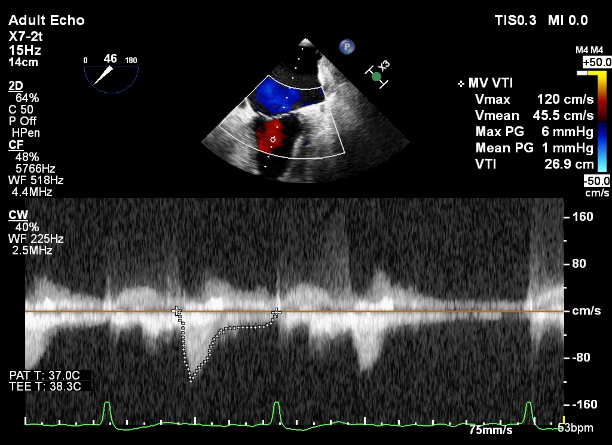

术前超声评估

术前超声诊断

LVOT-color:MR(重度),返流面积11.3cm2

肺静脉血流频谱呈收缩期反向

3D-color MV view:血流主要来源于2、3区

Qlab软件勾画估测瓣口面积约:6.16cm2

TEE LVOT切面返流量评估

TEE 4-Ch view返流量评估